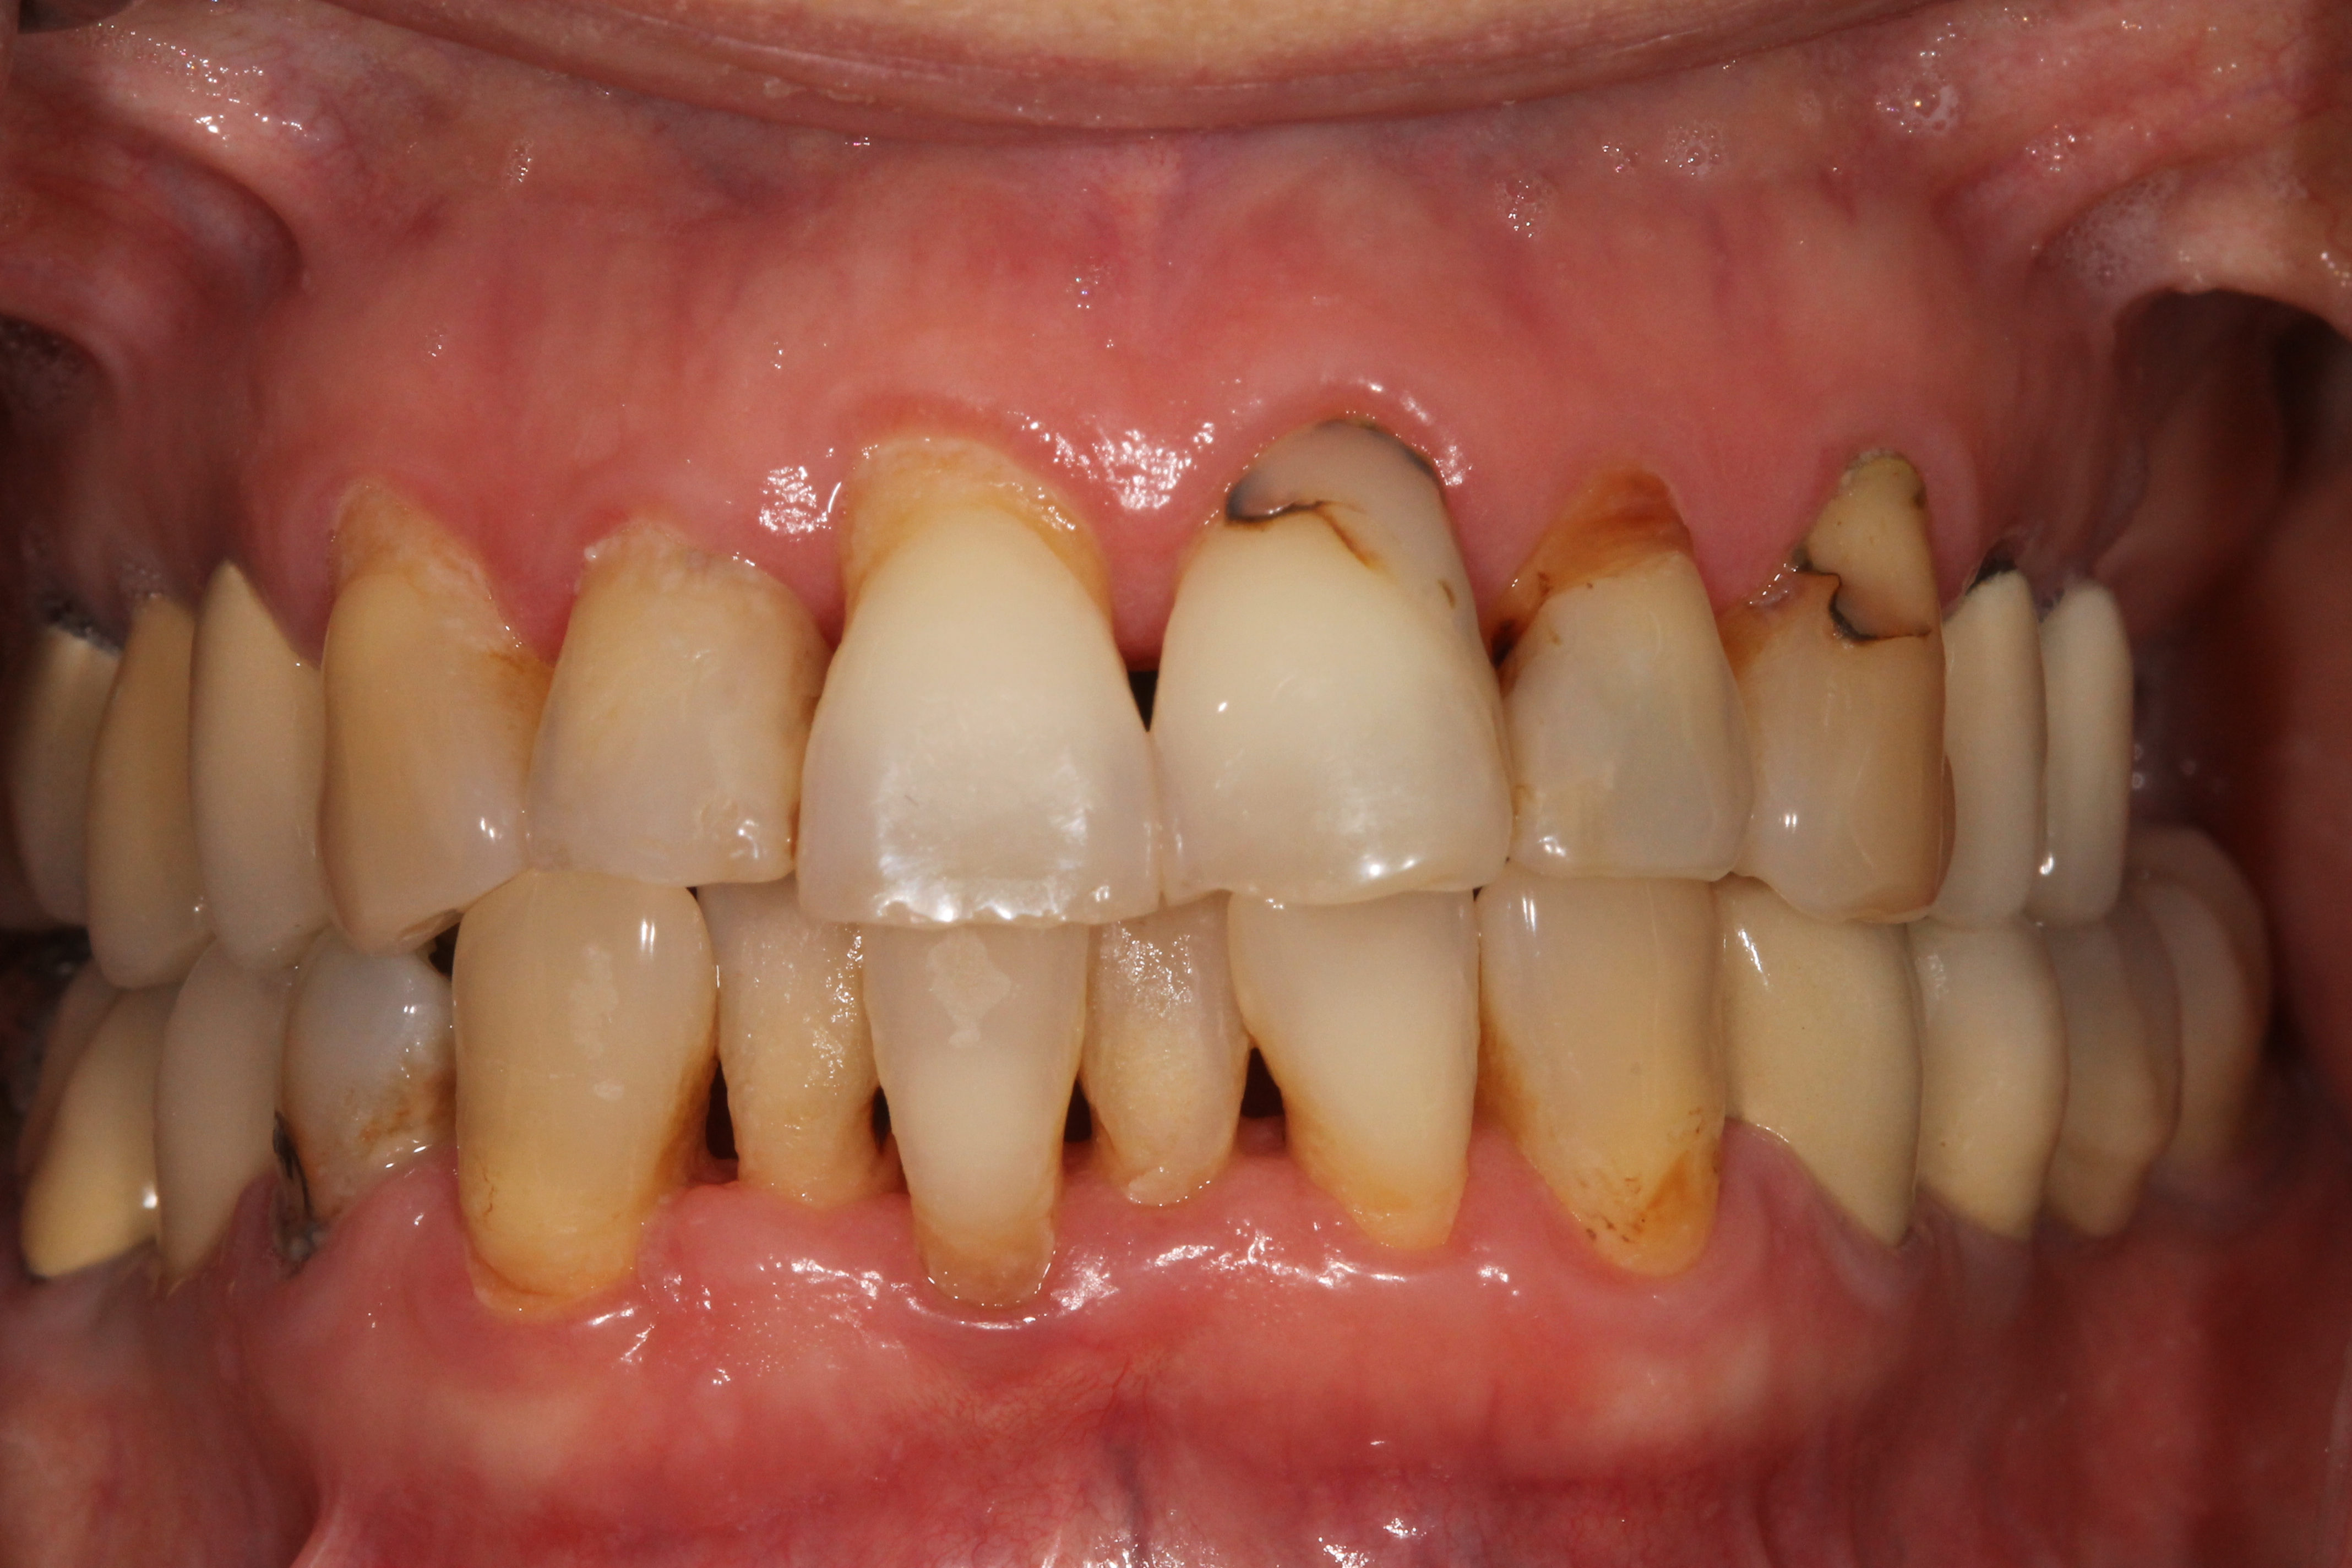

ΕΝΔΕΙΚΤΙΚΑ ΠΕΡΙΣΤΑΤΙΚΑ ΤΗΣ ΝΟΣΟΥ

προχωρημένο στάδιο

Περιοδοντίτιδα

Στην περιοδοντίτιδα η φλεγμονή από επιφανειακή που ήταν στην ουλίτιδα, επεκτείνεται βαθύτερα, προκαλεί αποκόλληση των ούλων από το δόντι, βάθυνση της ουλοδοντικής σχισμής, δημιουργία περιοδοντικών θυλάκων και σταδιακή καταστροφή του οστού που στηρίζει το δόντι.

Η σημαντική διαφορά μεταξύ ουλίτιδας και περιοδοντίτιδας είναι ότι στην περιοδοντίτιδα υπάρχει μόνιμη οστική καταστροφή, η οποία ποικίλει ανάλογα με την βαρύτητά της. Εάν η περιοδοντίτιδα δεν θεραπευθεί έγκαιρα ή εάν μετά τη θεραπεία παραμεληθεί η στοματική υγιεινή από τον ασθενή, η οστική καταστροφή επιδεινώνεται, το δόντι κινείται, είναι πιθανό να αλλάξει θέση, σταδιακά χάνει τη λειτουργικότητά του και συχνά καταλήγει σε εξαγωγή.